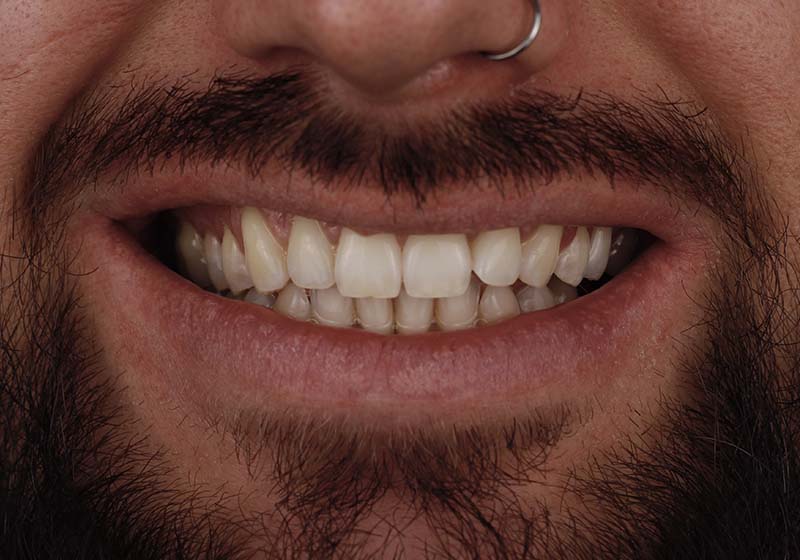

10 керамических виниров E-MAX цвета блич (Bleach)

Пациентка обратилась с жалобой на неудовлетворительную форму зубов и дисколорит. Перед началом лечения проведена HD-консультация и выполнено цифровое моделирование для показа будущего результата. В ходе лечения были изменены положение, формы и цвет зубов. Установлено 10 керамических виниров E-MAX цвета блич (Bleach).